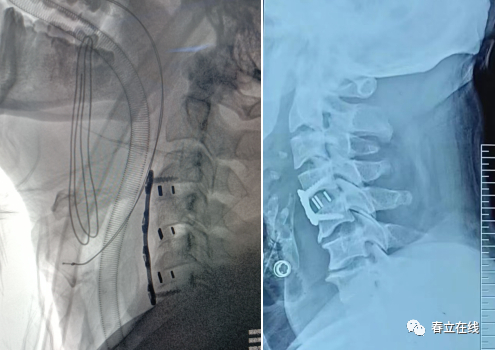

下面介绍一下前路固定的板-----颈椎前路IIIA板颈椎融合器

病例分享